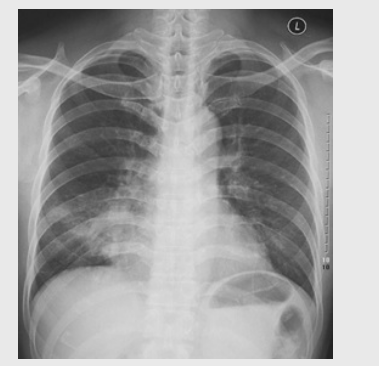

01卷-5.根據(jù)下圖請做出正確診斷

A.正常胸片

B.肺門淋巴結(jié)腫大

C.肺炎

D.主動脈型心(靴型心)